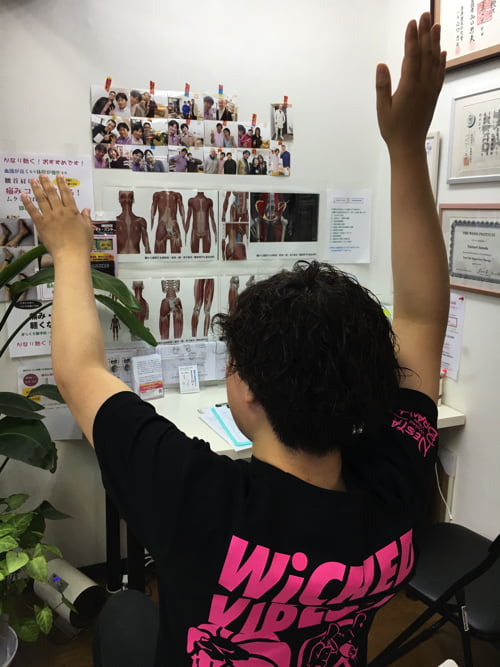

実際に腕を動かして頂くと

左腕をここまで上げると肩の付け根付近 の脇あたりに痛みが出てしまいます。

横から腕を上げる際もこんな感じで痛みがでて上がらない。

施術後すぐに両方の腕がここまでスムーズに上がるようになりました^^

そして更にこの部分を調整し直すと

もっとスムーズに動くようになりました^^